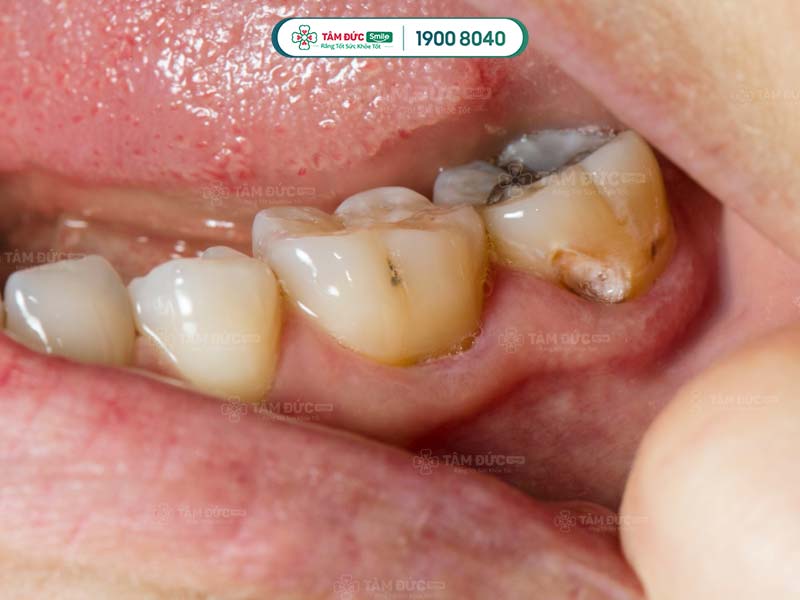

2.3. Sâu răng khôn do răng mọc ngầm, mọc lệch

- Răng khôn thường mọc ngầm, mọc lệch hoặc mọc ngang tạo khoảng hở với các răng bên cạnh.

- Thức ăn dễ bám vào lỗ sâu gây khó khăn trong việc vệ sinh, tạo điều kiện cho vi khuẩn tích tụ gây sâu răng, hôi miệng.

- Đây là nguyên nhân gây ra các bệnh lý như viêm nướu, viêm nha chu, mất răng vĩnh viễn,...